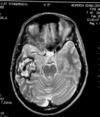

Describe the appearance of cavernous angiomas on MRI.

Shows target sign